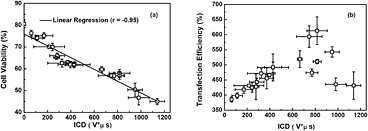

An interesting point worthy of notice is that, unlike nearly monotonic transitions of ICD and cell viability with the increasing p- and SPIO concentration, the variation trend of VEGF165 transfection efficiency seems much more complicated (figure 7(c)). To explore this phenomenon in depth, the correlations between transfection efficiency, cell viability and accumulated IC energy, were studied by analyzing the pooled experimental data. As shown in figure 8(a), significant linear correlation can be observed between the decrease of cell viability and the ICD enhancement. More importantly, it is clearly illustrated in figure 8(b) that, rather than the complex discrepant variations shown in figure 7(c), the DNA transfection efficiency initially increases linearly with the increasing ICD in a certain range. Then, after reaching its peak value at an ICD of about 820 V μs, DNA transfection efficiency tends to drop if the ICD increases continuously. As suggested by previous work, US-facilitated DNA transfection is mainly induced by sonoporation and high correlation could be observed between sonoporation pore size and the measured ICD (Qiu et al 2010). The transient pores generated on the cell membrane should be beneficial for cells to uptake the genetic material, which can lead to the enhancement of DNA transfection efficiency. However, if the IC energy exceeds a certain level (e.g. ICD > 820 V μs), overlarge pores might be generated, which in turn results in unrecoverable damage to cells. As a consequence, the cell viability would be impaired, thereby significantly lowering the DNA transfection efficiency.

Figure 8. Analyses for pooled experimental data. (a) Linear correlation between the cell viability and ICD; (b) the relationship between VEGF165 transfection efficiency and ICD. The figure plots the results for five replicated measurements.

Download figure: